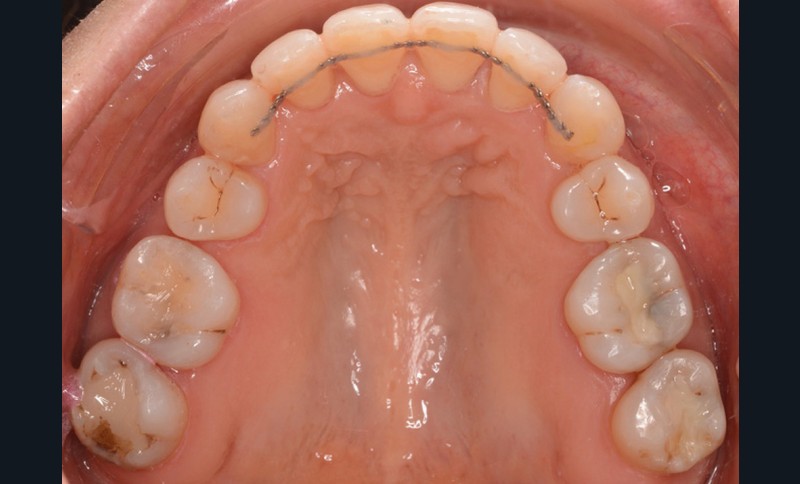

Sur le plan dentaire, la patiente est en classe III droite et gauche, canine et molaire de 6 mm, avec une occlusion inversée antérieure localisée à 11, 12 et 22. Elle présente une dysharmonie dents-arcades sévère, une agénésie d’une incisive mandibulaire est à signaler, et les troisièmes molaires ont été extraites à l’âge de 21 ans.